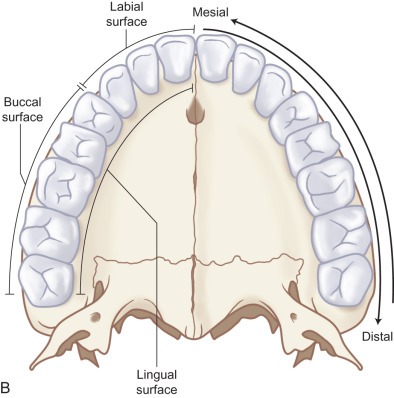

When considering the anatomy of dentoalveolar injuries, distinction must be made between primary and adult dentition as well as between teeth and the periodontium. A complete deciduous dentition includes two primary molars, a canine, and lateral and central incisors in each quadrant for a total of 20 teeth. The adult dentition includes three molars, two premolars, a canine and lateral and central incisors in each quadrant for a total of 32 teeth. At age 6, the adult first molars erupt posterior to the primary second molars, starting the ‘mixed dentition’ phase. A well-defined pattern of primary tooth exfoliation and adult tooth eruption ensues leaving one with mixed dentition until the last primary tooth exfoliates around 12 years of age ( Fig. 1.18.1 ).

All teeth are composed of enamel, dentin, dental pulp, and cementum ( Fig. 1.18.2 ). The periodontium is the structures that support the teeth, including the periodontal ligament, alveolar bone, and the overlying gingiva. As the name suggests, dentoalveolar injuries involve either or both dental structures along with alveolar bone. The term is oversimplified as injuries can include fractures through enamel, dentin, and exposure of the pulpal tissues and typically involve disruption of the periodontal ligament and lacerations of the overlying gingival mucosa.